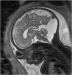

Abbildung 4: Pränatale Magnetresonanztomographie Fetus in der 32. SSW mit linksseitiger kongenitaler Zwerchfellhernie, koronale Schichtführung. Mit Hilfe der hier verwendeten Kontrastparameter können intrathorakal mit Mekonium gefüllten Darmanteile sehr hell dargestellt werden. Die Leber, sie ist etwas weniger hell als Mekonium, liegt intrabdominal. Am Hals ist auch die Glandula thyroidea zu erkennen. |

Abbildung 4: Pränatale Magnetresonanztomographie

Fetus in der 32. SSW mit linksseitiger kongenitaler Zwerchfellhernie, koronale Schichtführung. Mit Hilfe der hier verwendeten Kontrastparameter können intrathorakal mit Mekonium gefüllten Darmanteile sehr hell dargestellt werden. Die Leber, sie ist etwas weniger hell als Mekonium, liegt intrabdominal. Am Hals ist auch die Glandula thyroidea zu erkennen. |